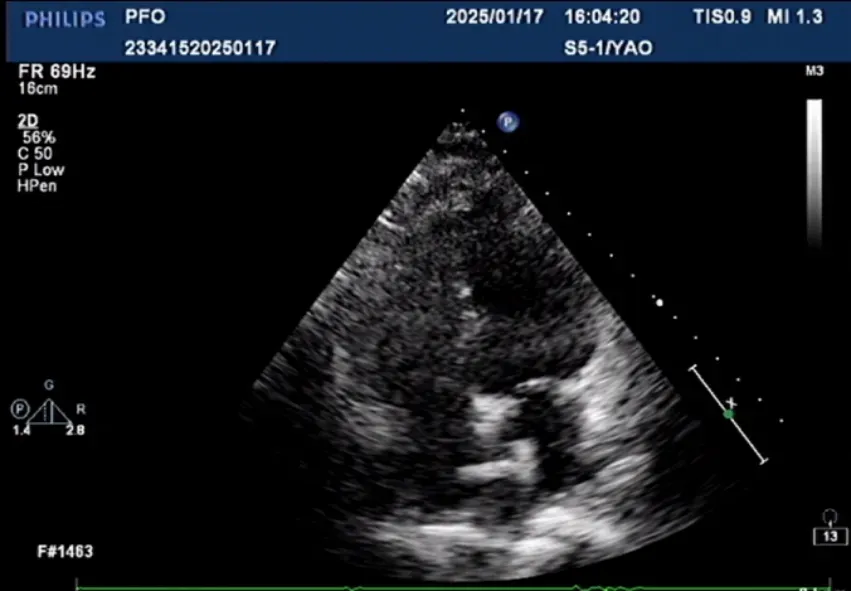

封堵傘左盤于左房內(nèi)釋放

封堵傘右盤釋放后